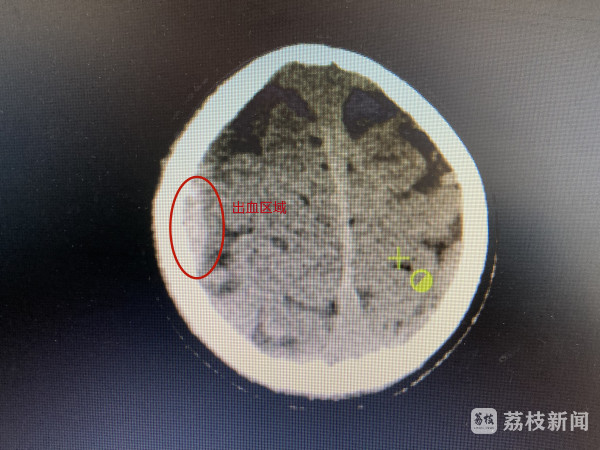

“孩子来的时候精神状态比较差,稍微动一下就会呕吐,嗜睡明显,跟她交流几乎没有回应。”淮安市妇幼保健院小儿外科主治医师王晓敏说。根据小涵的情况,立即让家人带其做了头部CT检查。“做了CT以后就确诊是双侧顶部硬膜外血肿,这个相比外伤算是比较重的,出血量中等,如果再严重就要考虑开颅手术,但孩子很小,现在也相对可控,所以我们给孩子进行了止血、脱水、消肿治疗,并对她的情况密切关注。”王晓敏说。

在医生的精心治疗下,小涵的病情已经好转,最近一次CT显示,她颅内的出血已经明显吸收,再观察治疗一段时间就可以出院了。记者从小涵家长处了解到,因金毛犬当时没有栓绳,所以此次治疗费用由狗主人承担。